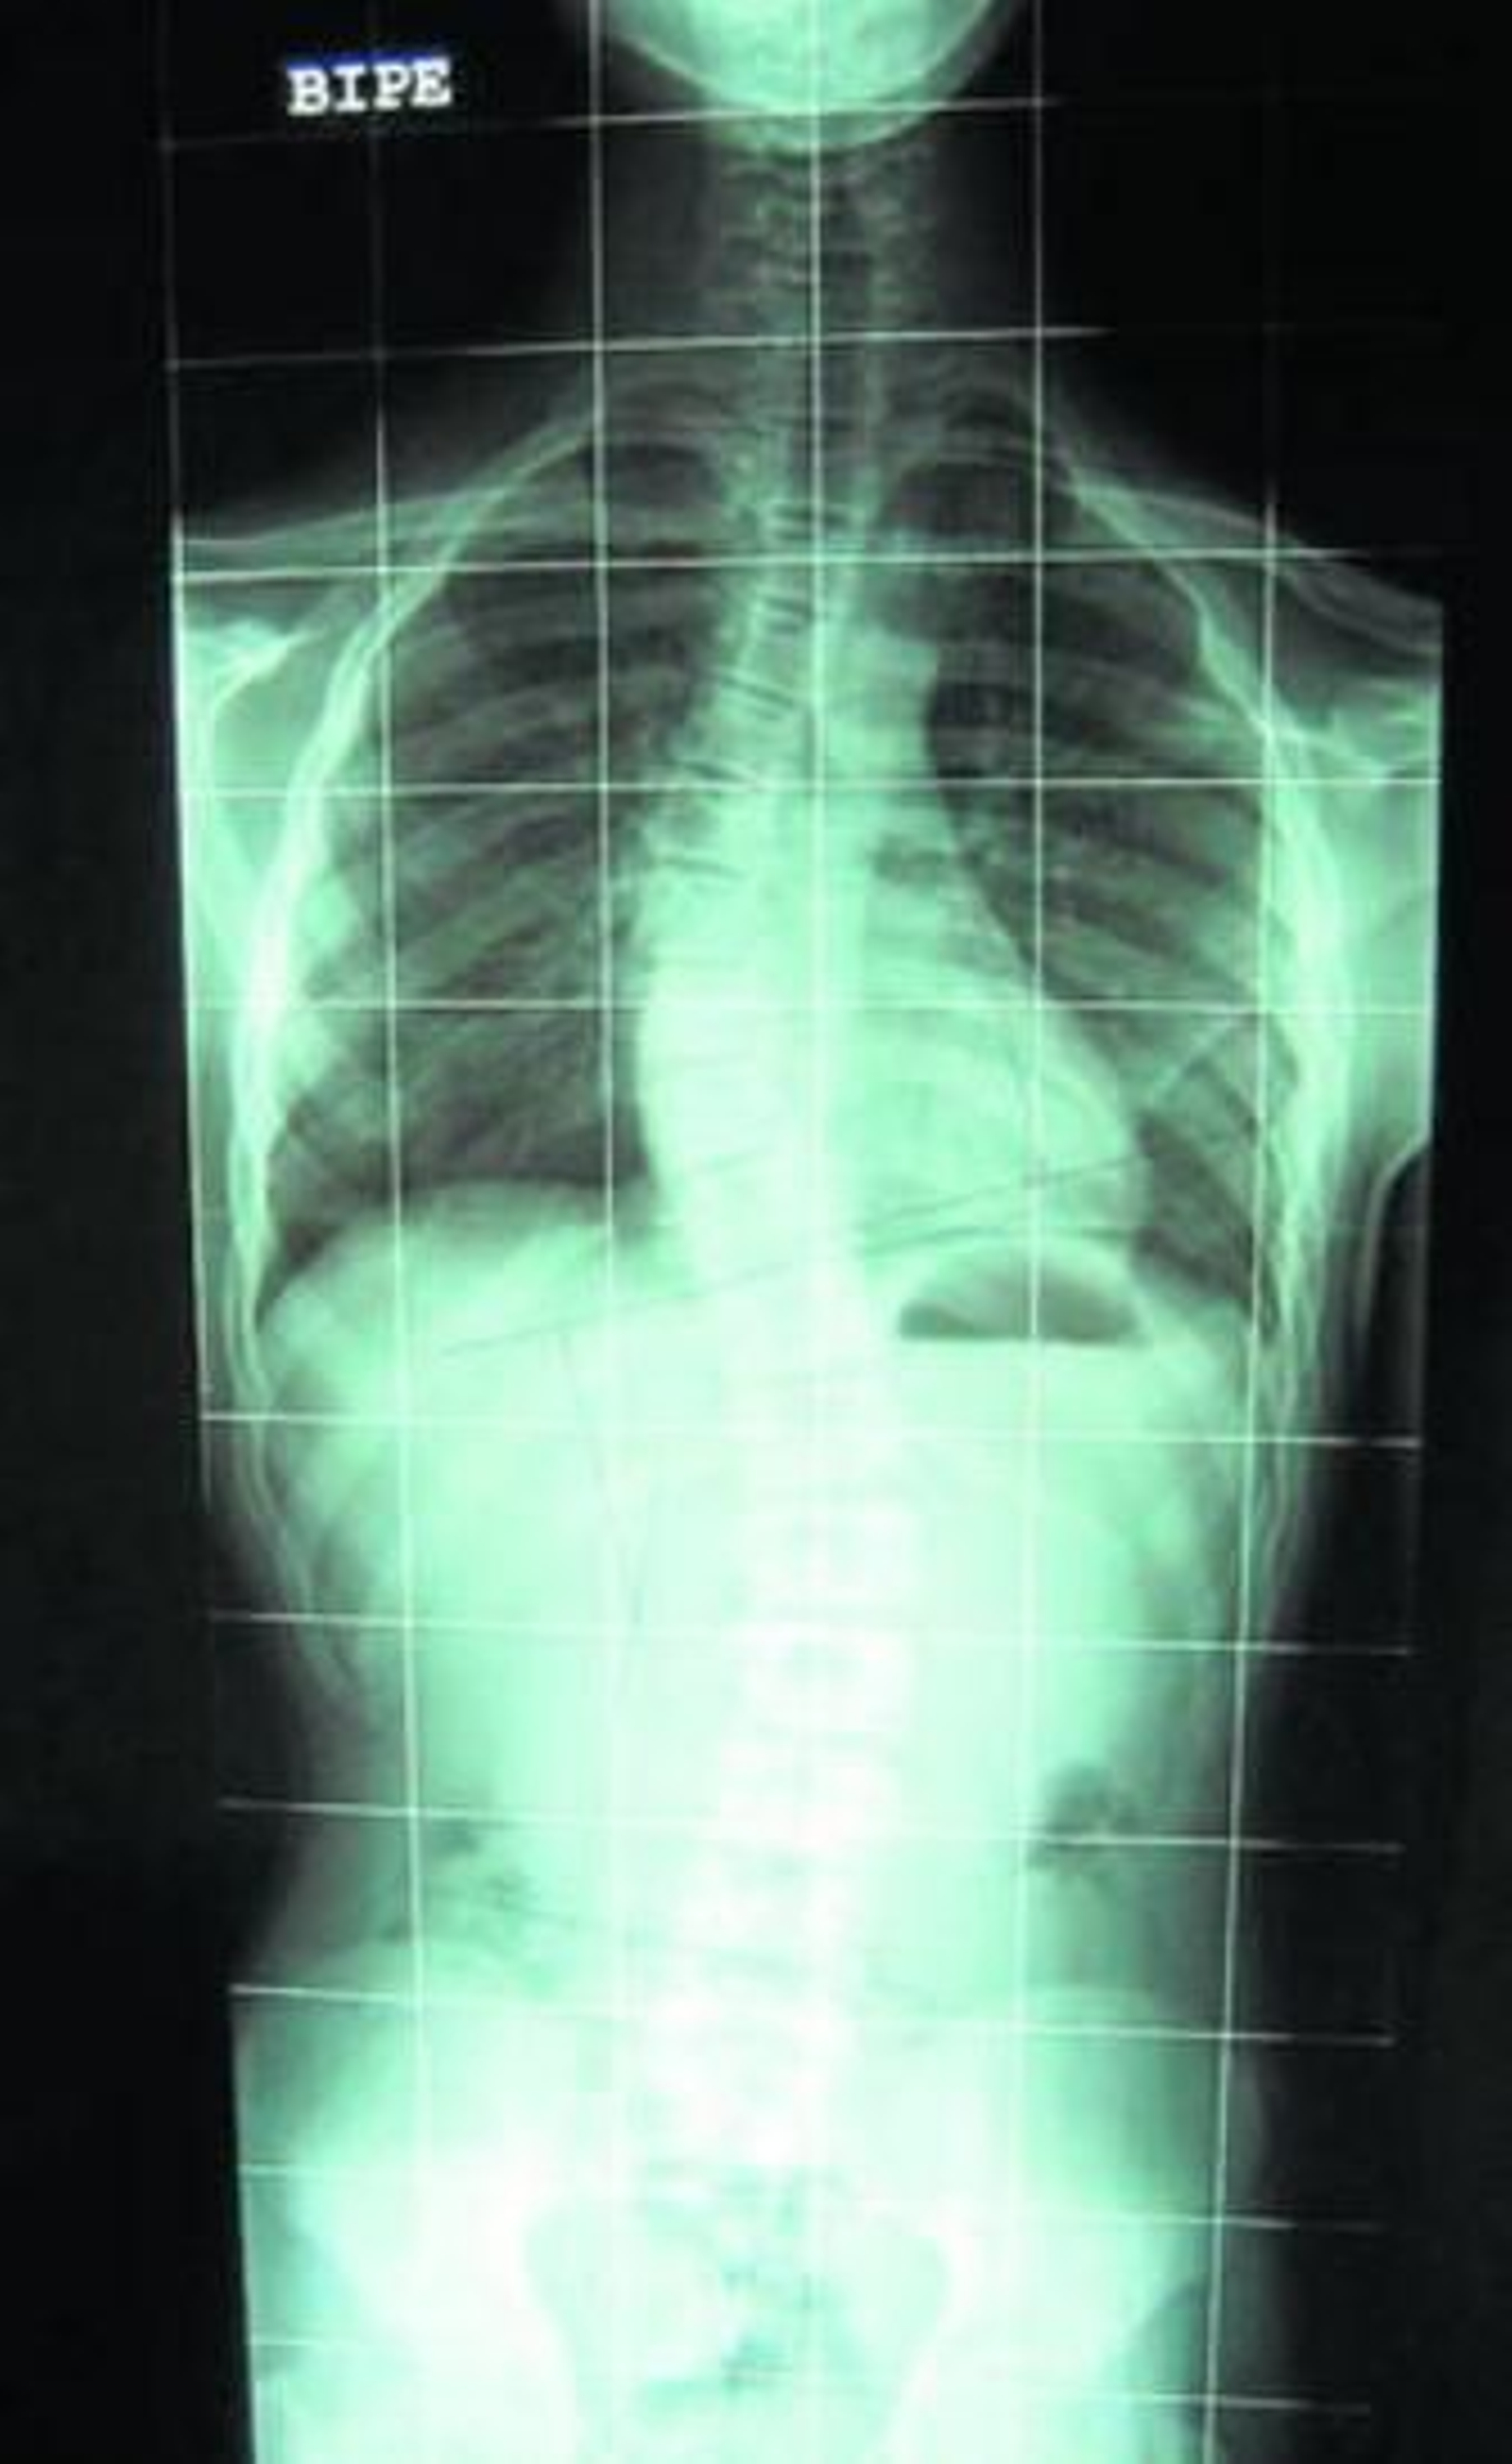

Cuando se sospeche esta lesión, se debe realizar una telerradiografía de columna tanto de frente como lateral con el niño de pie. Así se mide la deformidad. Esto nos servirá como punto de partida para el seguimiento y futuras radiografías y poder compararlas.